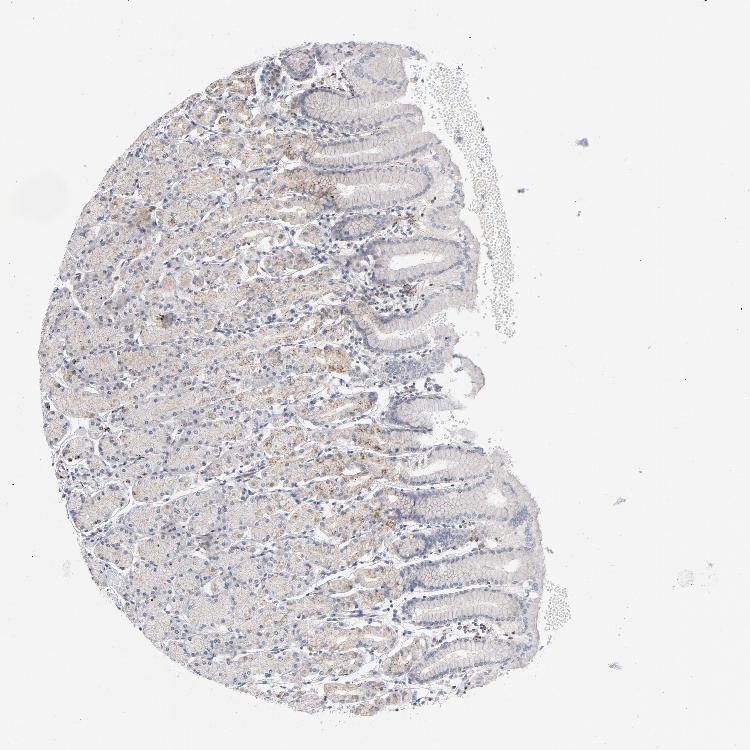

TISSUE PRIMARY DATA STOMACH Show tissue menu

STOMACH 1 - Antibody stainingi

Antibody staining in the annotated cell types in the current human tissue is reported as not detected, low, medium, or high, based on conventional immunohistochemistry profiling in selected tissues. This score is based on the combination of the staining intensity and fraction of stained cells.

Each image is clickable and will lead to virtual microscopy that enables deeper exploration of all samples and also displays staining intensity scores, fraction scores and subcellular localization as well as patient and tissue information for each sample.

Antibody CAB004204Antibody CAB080295

Glandular cells MediumMedium